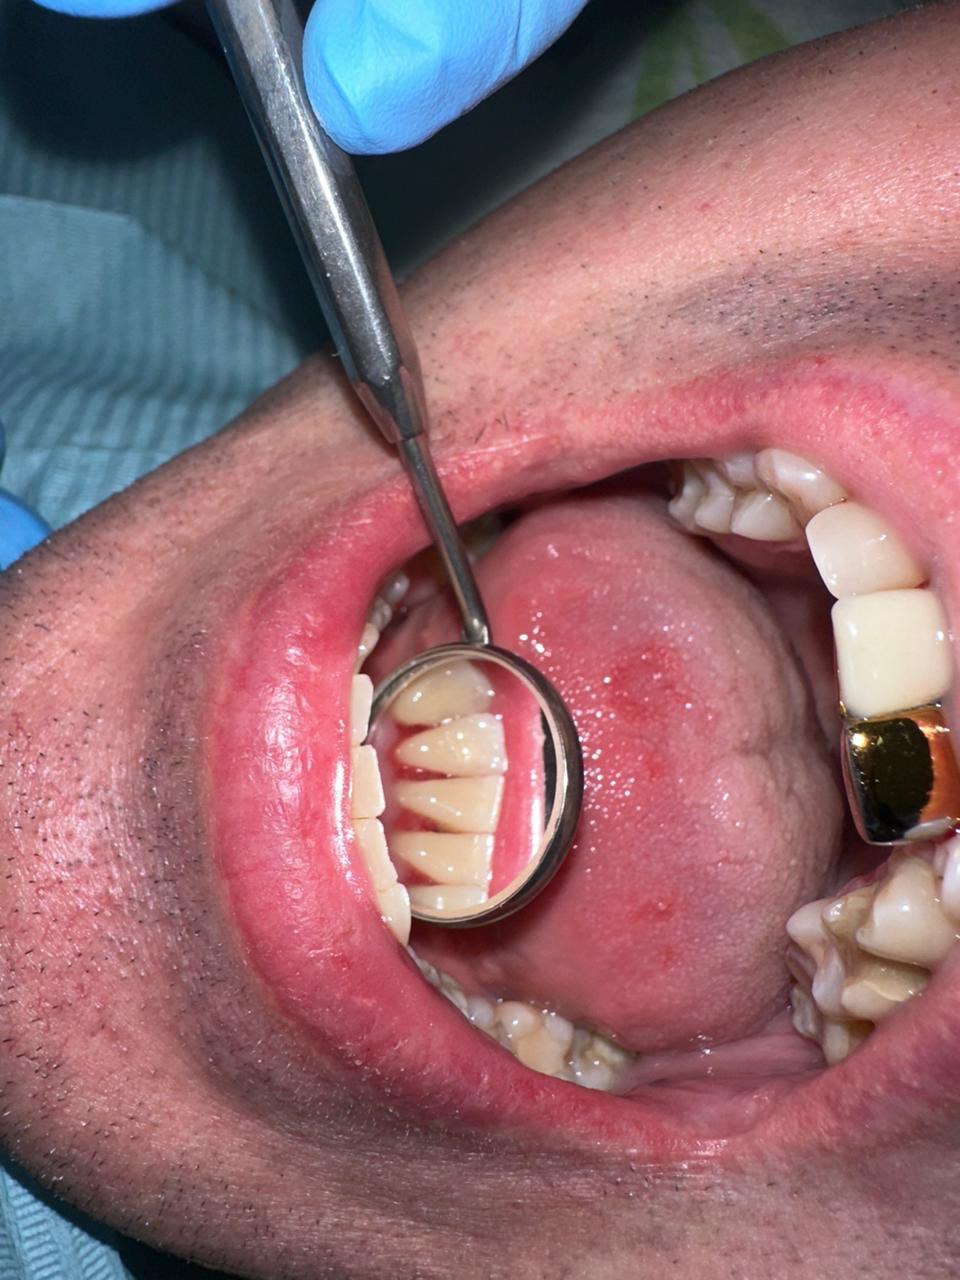

Снятие зубных отложений и зубного камня

Ультразвуковая чистка зубов - снятие зубного камня с помощью ультразвукового скайлера.

| A22.07.002 Ультразвуковое удаление наддесневых и поддесневых зубных отложений в области зуба (легкой степени) | 300 | |

| A22.07.002.001 Ультразвуковое удаление наддесневых и поддесневых зубных отложений в области зуба (средней степени) | 400 | |

| A22.07.002.002 Ультразвуковое удаление наддесневых и поддесневых зубных отложений в области зуба (тяжелой степени) | 500 | |